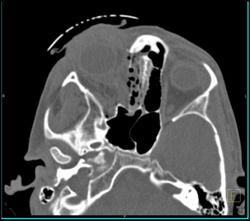

Orbital Trauma